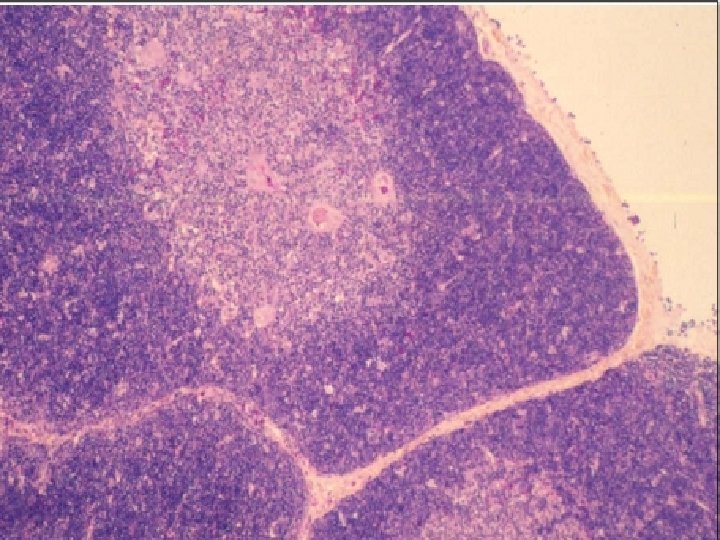

Thymus is the only discrete central lymphoid organ in humans. It produces only T lymphocyte precursors and has no lymphoid nodules. Its reticular cells derive from endoderm and produce no reticular fibers. It is the only organ containing Hassall’s corpuscles. Its age-dependent structural atrophy or involution is also unique among lymphoid organs. 2 lobes are joined and covered by a thin loose connective tissue capsule that penetrates the lobes as septa, dividing each lobe into incomplete lobules. Cortex. This is the dark-staining periphery of each lobule. Small lymphocytes predominate

Medulla. In effect, each thymic lobe has a single medulla that extends into the core of each of the lobules. The light staining of the medulla reflects the presence of more epithelial reticular cells and fewer lymphocytes than in the cortex. The spheric Hassall’s corpuscles (30 -150 m in diameter) are composed of concentric layers of flattened epithelial reticular cells. With age, cells in the core of the corpuscles may die and calcify. Functions: 1. T lymphocyte production. 2. Blood -thymus barrier. 3. Production hormone - thymosin

Thymus • • n Hassal’s Corpuscles Capsule Lobules Cortex Medulla